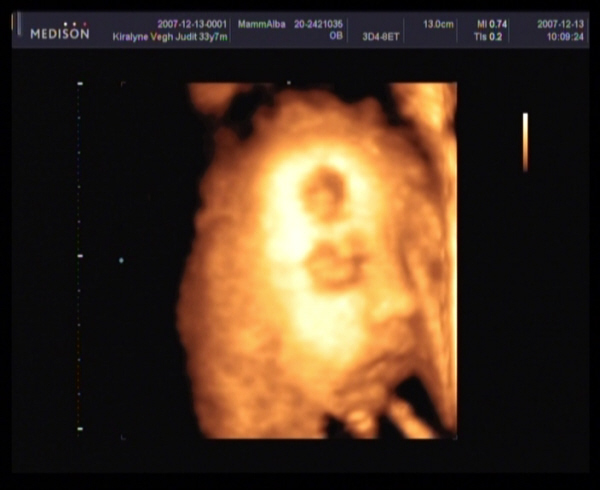

Judy,

gyere a képekkel!!!! Nagyon kíváncsi vagyok Barbikára!!!!!